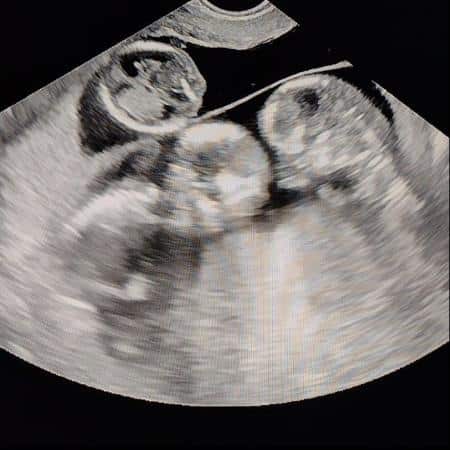

Ao descobrir que estava grávida de trigêmeos, Lívia Magalhães ficou em choque por vários dias.

“A gestação é considerada de alto risco, tanto por ser trigemelar quanto pela minha pouca idade e tamanho. Eu tenho 1,50 m e peso 45 kg. Completei 19 anos este mês. Fico pensando: “Como vai caber três crianças dentro de mim?” “Demoramos a aceitar”, disse a técnica em enfermagem que sonha ser psicóloga.

Não há nenhum caso de gêmeos na minha família, nem na do Wylker. Ainda não consegui ver os sexos, mas dois bebês são idênticos e um não. Ou seja, tenho os dois tipos de gestações gemelares ao mesmo tempo. Deus me escolheu, não tem outra explicação. Minhas maiores preocupações são o parto e a questão financeira. Estou desempregada e minha mãe também. Ela trabalhava como secretária em um escritório de advocacia, mas foi demitida na pandemia. Me preocupo em conseguir comprar as coisas antes de eles nascerem. É fralda em dose tripla, é enxoval, é muita coisa. Também me preocupo que corra tudo bem no parto, que eles nasçam saudáveis, que não passem muito tempo na UTI.